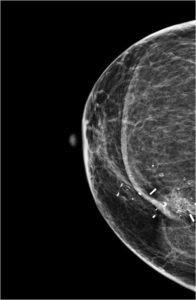

CA right breast; lumpectomy done; on follow up. What type of calcification is seen?

SUTURE CALCIFICATIONS

Suture material may become calcified, resulting in suture calcifications. Suture calcifications are usually seen at a known surgical site, and the calcifications may be linear or tubular. Knots may be demonstrated. Suture calcifications are likely due to delayed resorption of catgut sutures, which can provide a matrix on which calcium can precipitate

Focal architectural distortion with retraction of the overlying skin is seen in upper inner quadrant of right breast – consistent with post surgical changes. Adjacent to this multiple calcifications with central lucency noted. Surgical clips noted in upper inner quadrant of right breast. Multiple rounded and linear calcifications noted in upper inner quadrant of right breast. Vascular calcification noted in right breast.